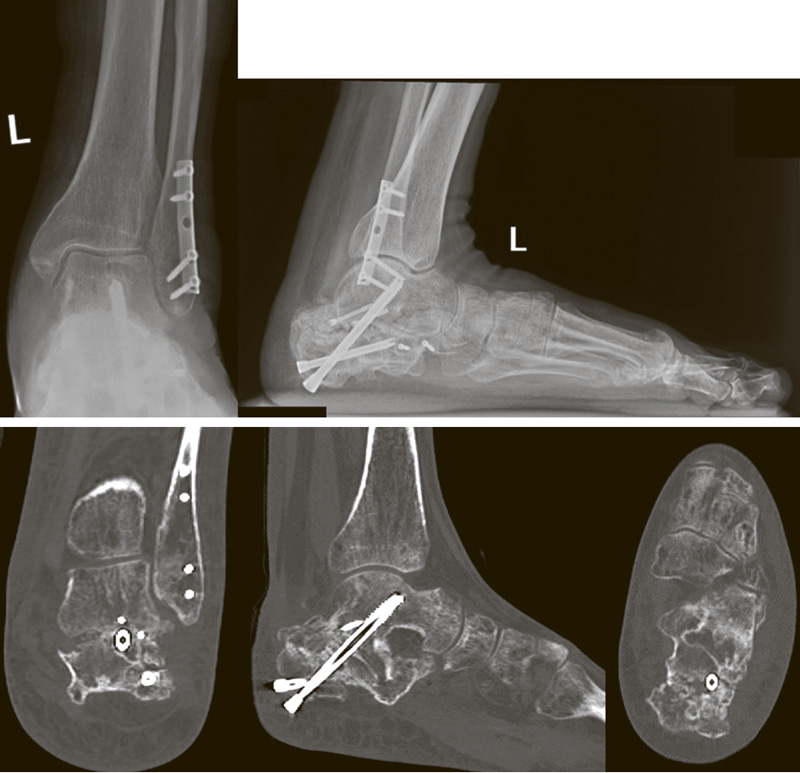

Хирургическое лечение застарелых переломов пяточной кости: обзор литературы

Последствия переломов пяточной кости вызывают стойкую инвалидизацию пациентов и снижение качества их жизни. Типичными проявлениями выступают деформация заднего отдела стопы, плоскостопие и подтаранный артроз. Стойкие посттравматические деформации с течением времени приводят к возникновению патологической биомеханики стопы и нарушению кинематики и кинетики нижних конечностей и таза.